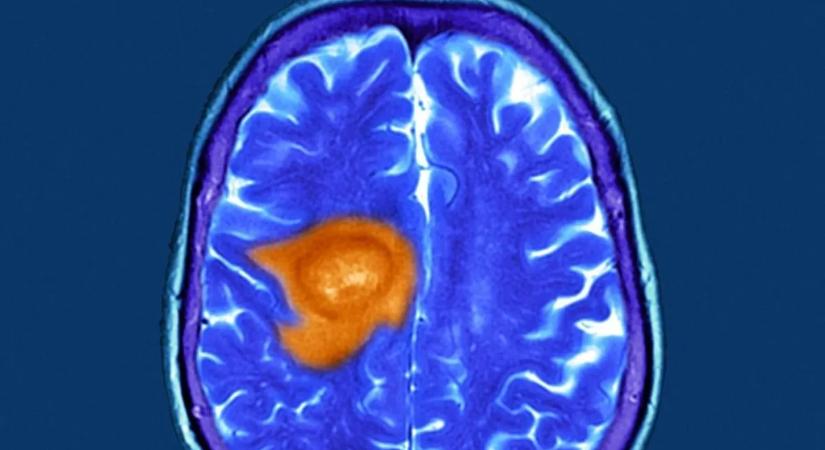

Új Remény a glioblasztómás betegeknek.